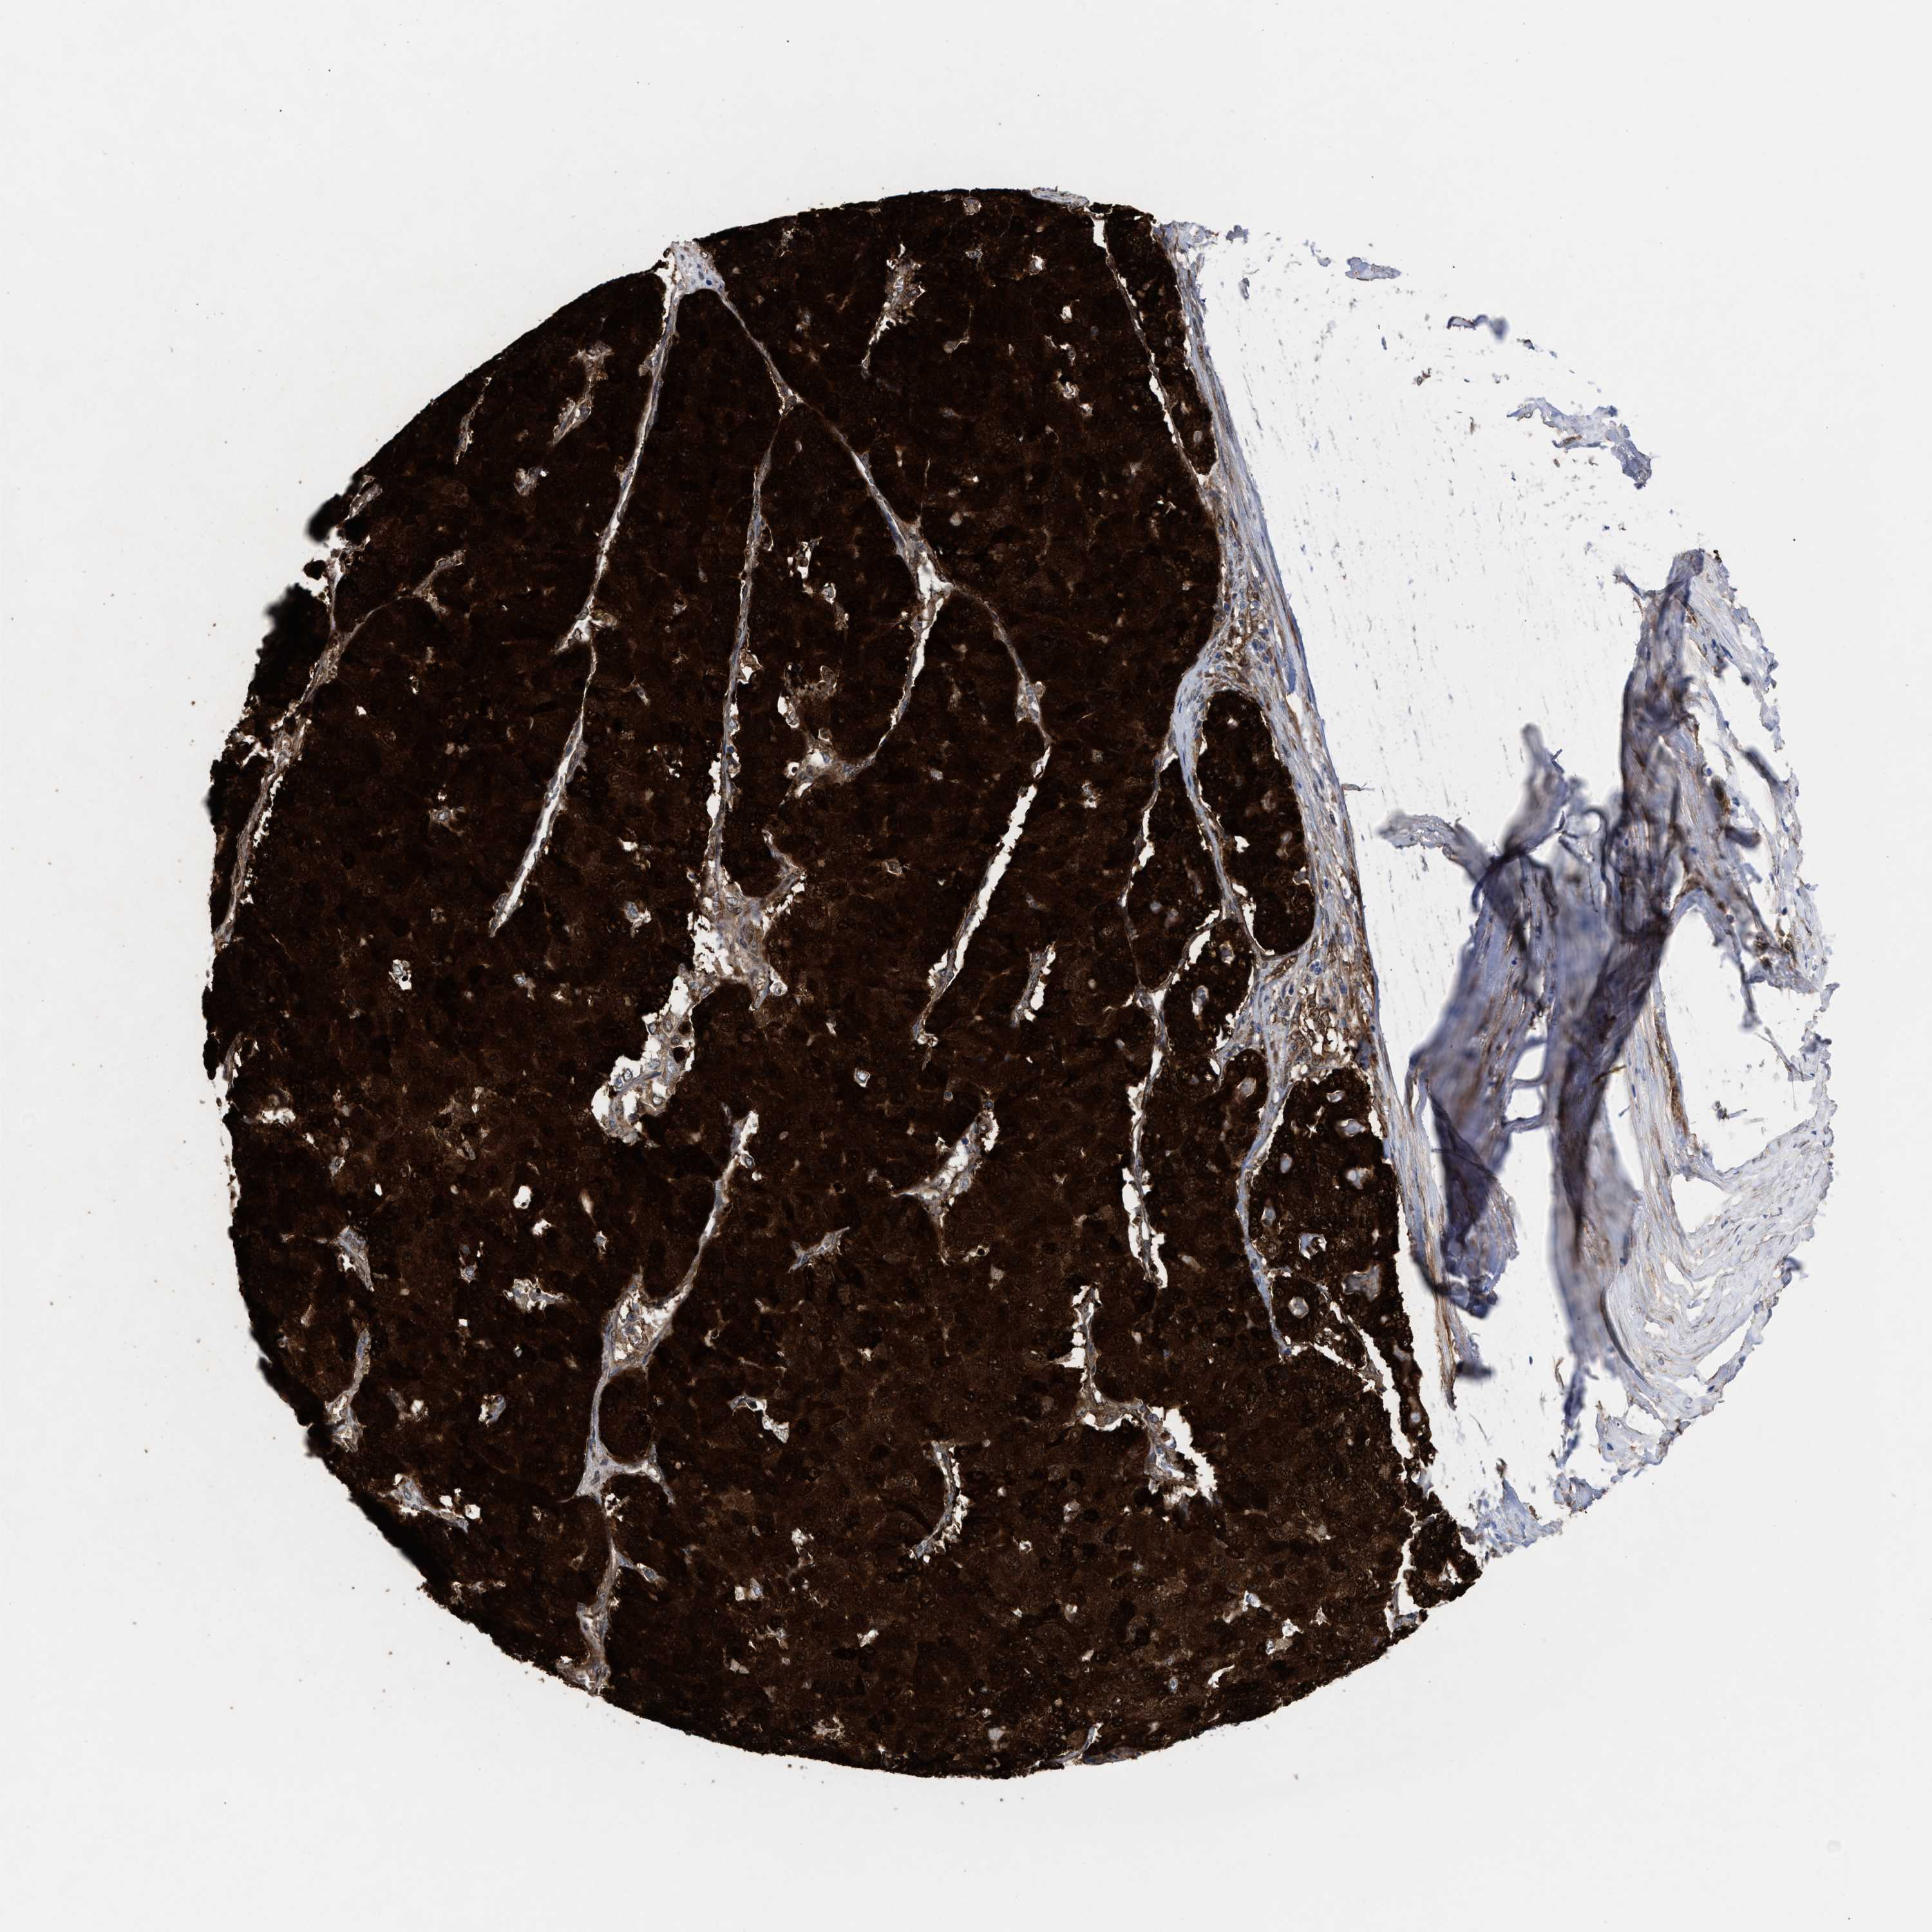

PANCREATIC CANCER - Protein expressioni

A mouse-over function shows sample information and annotation data. Click on an image to view it in a full screen mode. Samples can be filtered based on level of antibody staining by selecting one or several of the following categories: high, medium, low and not detected. The assay and annotation is described here.

Note that samples used for immunohistochemistry by the Human Protein Atlas do not correspond to samples in the TCGA dataset.

Antibody stainingi

Antibody staining in the annotated cell types in the current human tissue is reported as not detected, low, medium, or high, based on conventional immunohistochemistry profiling in selected tissues. This score is based on the combination of the staining intensity and fraction of stained cells.

Each image is clickable and will lead to virtual microscopy that enables deeper exploration of all samples and also displays staining intensity scores, fraction scores and subcellular localization as well as patient and tissue information for each sample.

Antibody HPA022012

Antibody HPA028742

Antibody CAB017479

Staining

High

Medium

Low

Not detected

Intensity

Strong

Moderate

Weak

Negative

Quantity

>75%

75%-25%

<25%

None

Location

Nuclear

Cytoplasmic/membranous

Cytoplasmic/membranous,nuclear

Adenocarcinoma, NOS

Adenocarcinoma, metastatic, NOS